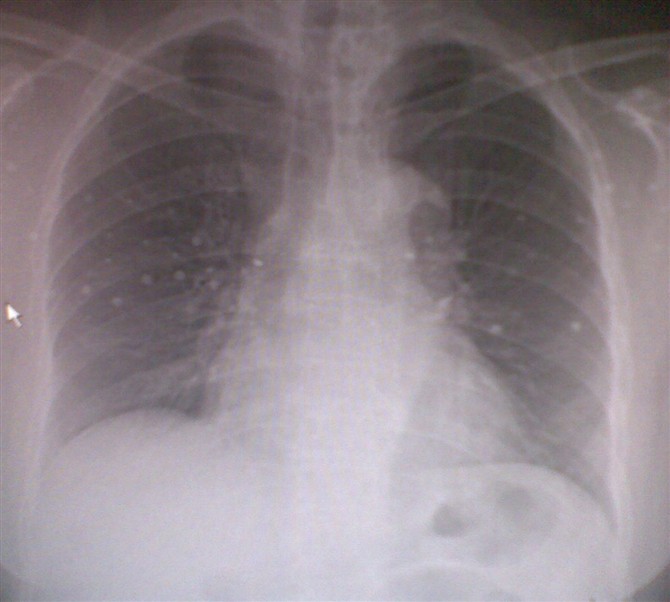

鼻骨外伤   体检气管右移无症状  跟骨骨折望告知轴位摄片的办法[emb18]

鼻骨骨折,胸部未见外伤,跟骨轴位怎么摆你可以查一下投照书。

气管右侧移位,并轻度变窄,其临近左侧纵隔内似见不规则斑块状致密影,是否纵隔内有肿块,胸内甲状腺?ct吧,或结合病史。其它不再缀述。

鼻骨骨折,胸部未见明显异常,跟骨轴位投照法可参照6楼意见。